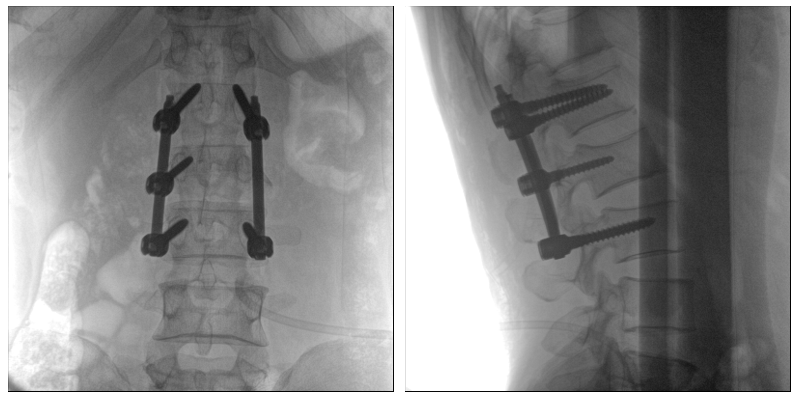

從下圖中可以看到二維影像能夠提供目標(biāo)區(qū)域在某一個(gè)平面的重疊影像,雖然因?yàn)槿梭w不同組織的密度差異,使得圖像具有較為豐富的信息量,但組織間的相互重疊還是會(huì)出現(xiàn),諸如空間位置等眾多信息在影像中遺失或不可辨認(rèn)的情況,影響了醫(yī)生對(duì)信息的收集與應(yīng)用。

術(shù)中二維影像